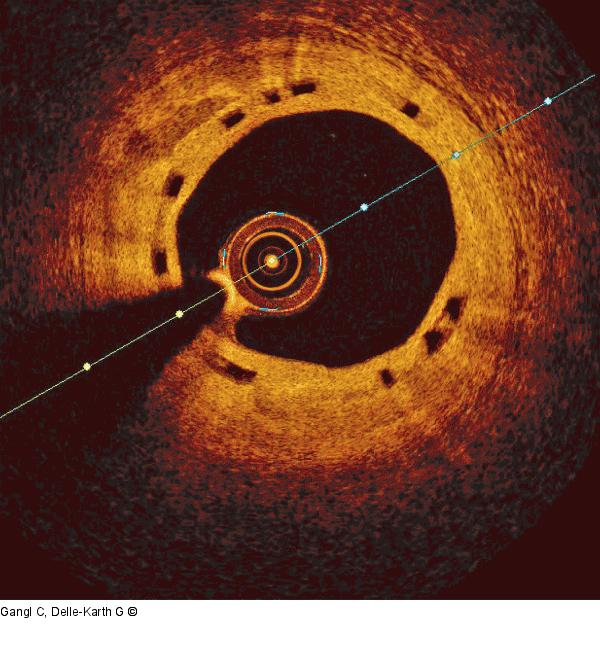

Abbildung 4: ABSORB-Scaffold OCT-Aufnahme des ein Jahr zuvor implantierten ABSORB-Scaffolds |

Abbildung 4: ABSORB-Scaffold

OCT-Aufnahme des ein Jahr zuvor implantierten ABSORB-Scaffolds |